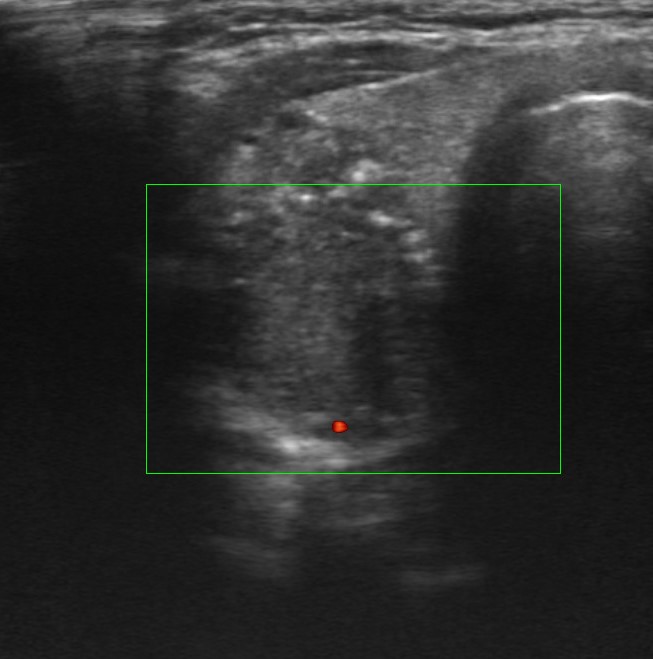

Hallazgos ecográficos

Nódulo de 16,9×15,1 mm, sólido, hipoecoico, de bordes mal definidos, más alto que ancho y con microfocos ecogénicos y calcificación periférica en anillo. Se clasifica como TIRADS 5, altamente sospechoso de malignidad e indicativo de PAAF al superar los 10 mm.